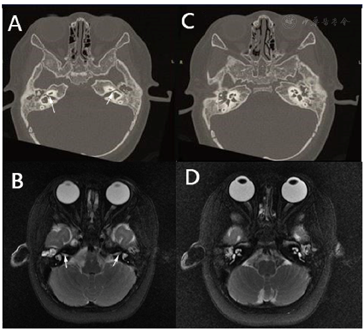

①听力学检查:声导抗:右耳B型鼓室图,左耳A型鼓室图;ABR:双耳100 dBnHL均未引出反应;40HzAERP:左耳阈值120 dB nHL,右耳120 dB nHL未引出反应;DPOAE:双耳各频率均未引出;ASSR(500Hz、1000Hz、2000Hz、4000Hz):左侧94-114-107-101 dB eHL,右侧最大强度未引出反应。②超声检查:心脏超声检查提示心脏结构及功能均未见异常;③颞骨CT:双侧外耳道正常,双侧听小骨结构存在,砧骨长脚及镫骨纤细。左侧水平半规管呈单囊状,前庭窗未发育。双侧面神经走行异常。耳蜗形态正常,内听道相对狭窄,双侧前庭水管无扩大。双侧乳突气化不良、气房及鼓室内见密度增高影,考虑双侧中耳乳突炎。④颅脑MRI:脑室系统形态及大小未见明显异常,脑沟、裂、池未见明显异常。⑤内耳MRI水成像:双侧蜗神经纤细,双侧面神经纤细可能,考虑发育异常,双侧前庭及水平半规管发育异常,双侧内听道对称、狭窄。⑥胸部正位片:胸部未见其他异常。

患者于入院后行双耳人工耳蜗植入。术中作耳后小切口,筛区入路逐层磨除骨质,见乳突气化差,其内黏膜水肿、增厚、分泌物填充,以乳突天盖为标志向前定位上鼓室,暴露畸形的砧骨短突,未见外半规管。面神经走形异常,水平段面神经15度斜形向后进入乳突腔,无明显锥曲段。经面神经隐窝暴露圆窗,见圆窗膜面积较正常小。将人工耳蜗接收器置入颞骨骨槽并固定。后经圆窗入路将耳蜗电极全部插入,植入顺利,安置电极线后逐层缝合。测试显示电极阻抗好,部分电极术中神经反应遥测(Nerve response telemetry,NRT)反应好。敷料覆盖。变换体位,右耳朝上,常规消毒铺巾。乳突气化差,面神经走行异常,解剖面神经及鼓索神经,同法植入右侧耳蜗,电极植入顺利,测试显示电极阻抗及部分电极NRT反应好。